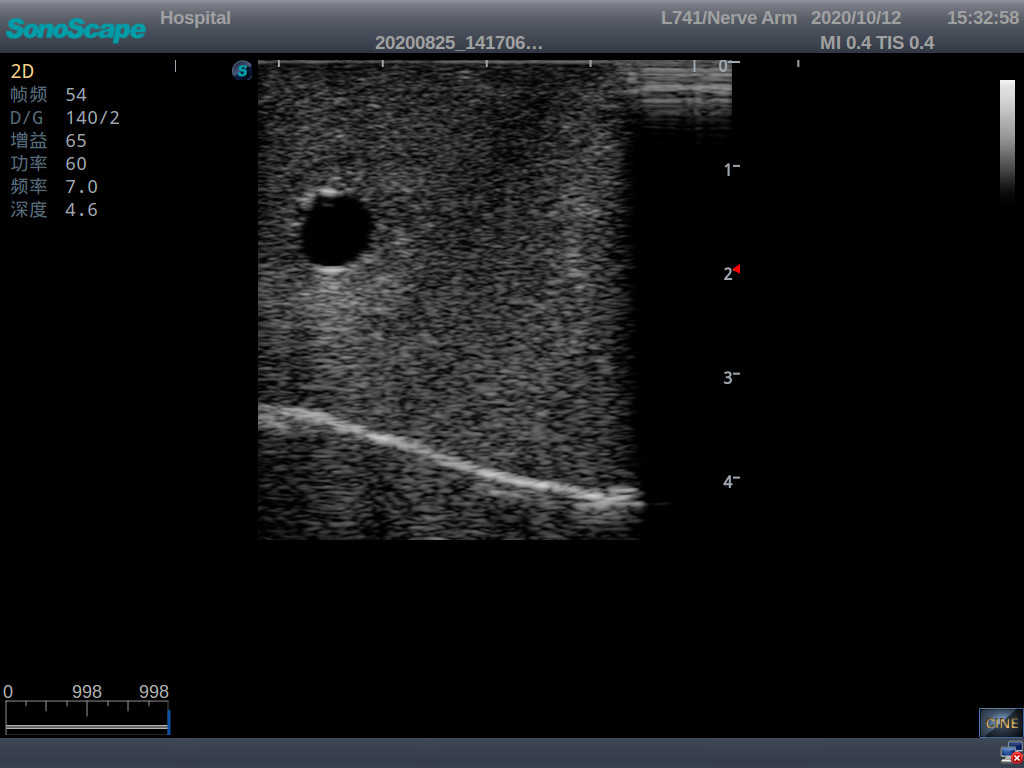

2) The puncture module supports using a clinical real ultrasound machine to observe clear images such as right internal jugular vein, right common carotid artery, superior vena cava, right brachiocephalic vein, right brachiocephalic trunk, right subclavian vein, right subclavian artery, etc.

3) The puncture pad at the arm is made of high-molecular ultrasound material, close to real skin. It can support the use of real ultrasound machines, and the images of tissue structures (skin, subcutaneous tissue, blood vessels) under ultrasound are clear and real